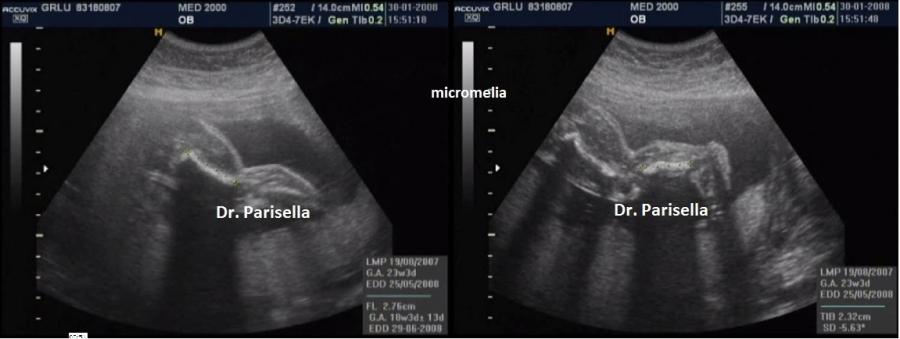

E' la forma più comune di nanismo osteodisplasico microcefalico ed è caratterizzata da nanismo micromelico, microcefalia e ritardo mentale, malformazioni muscolo scheletriche e viscerali. E' anche detta nanismo a testa di uccello  perchè la microcefalia di questi pazienti, con fronte e mento sfuggenti e naso prominente, fa somigliare il loro capo a quello di un uccello. Altre anomalie frequenti del viso sono: occhi particolarmente grandi e distanti, faccia ampia, orecchie ad impianto basso o malformate, micrognatia. Talora sono stati descritti anche clinodattilia, displasia dei fianchi, dislocazione della testa del radio, e altre anomalie più rare.